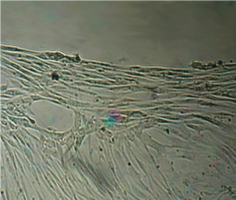

Исследование проведено на первичных культурах дермальных фибробластов и мезенхимальных стромальных клетках человека 4-12 пассажа.

Культуру дермальных фибробластов получали из кожно-мышечной ткани, а культуру мезенхимальных стромальных клеток – из фрагментов крыши черепа абортусов сроком 6-10 недель методом первичных эксплантатов (рис. 1, 2).

Вид монослоя и структура клеток не отличались от обычных в течение всех четырех суток наблюдения (рис. 32).

Цитоплазма представлялась гомогенной (рис. 33). Большинство клеток имели одно центрально расположенное ядро правильной округлой формы с 1 или 2 ядрышками.